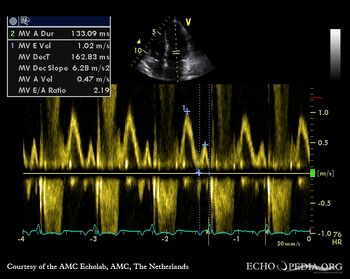

E00509.jpg

Continuous-wave doppler signal: dynamic gradient in LVOT Pulsed-wave doppler signal of transmitral flow